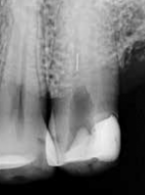

Powtórne leczenie kanałowe, dekompresja torbieli i jej późniejsze usunięcie ze sterowaną regeneracją kości, czyli krótka historia długiego leczenia zębów 35 i 36

Zobacz więcej

Michał Rawicki

Inwazyjna resorpcja przyszyjkowa zęba 37

lek. stom. Jacek Bilbin

Perforacje jako powikłanie leczenia endodontycznego – postępowanie kliniczne

Joanna Grącka‑Mańkowska, Aleksandra Palatyńska‑Ulatowska, Halina Pawlicka

Clinical management of root perforations – complications of endodontic treatment